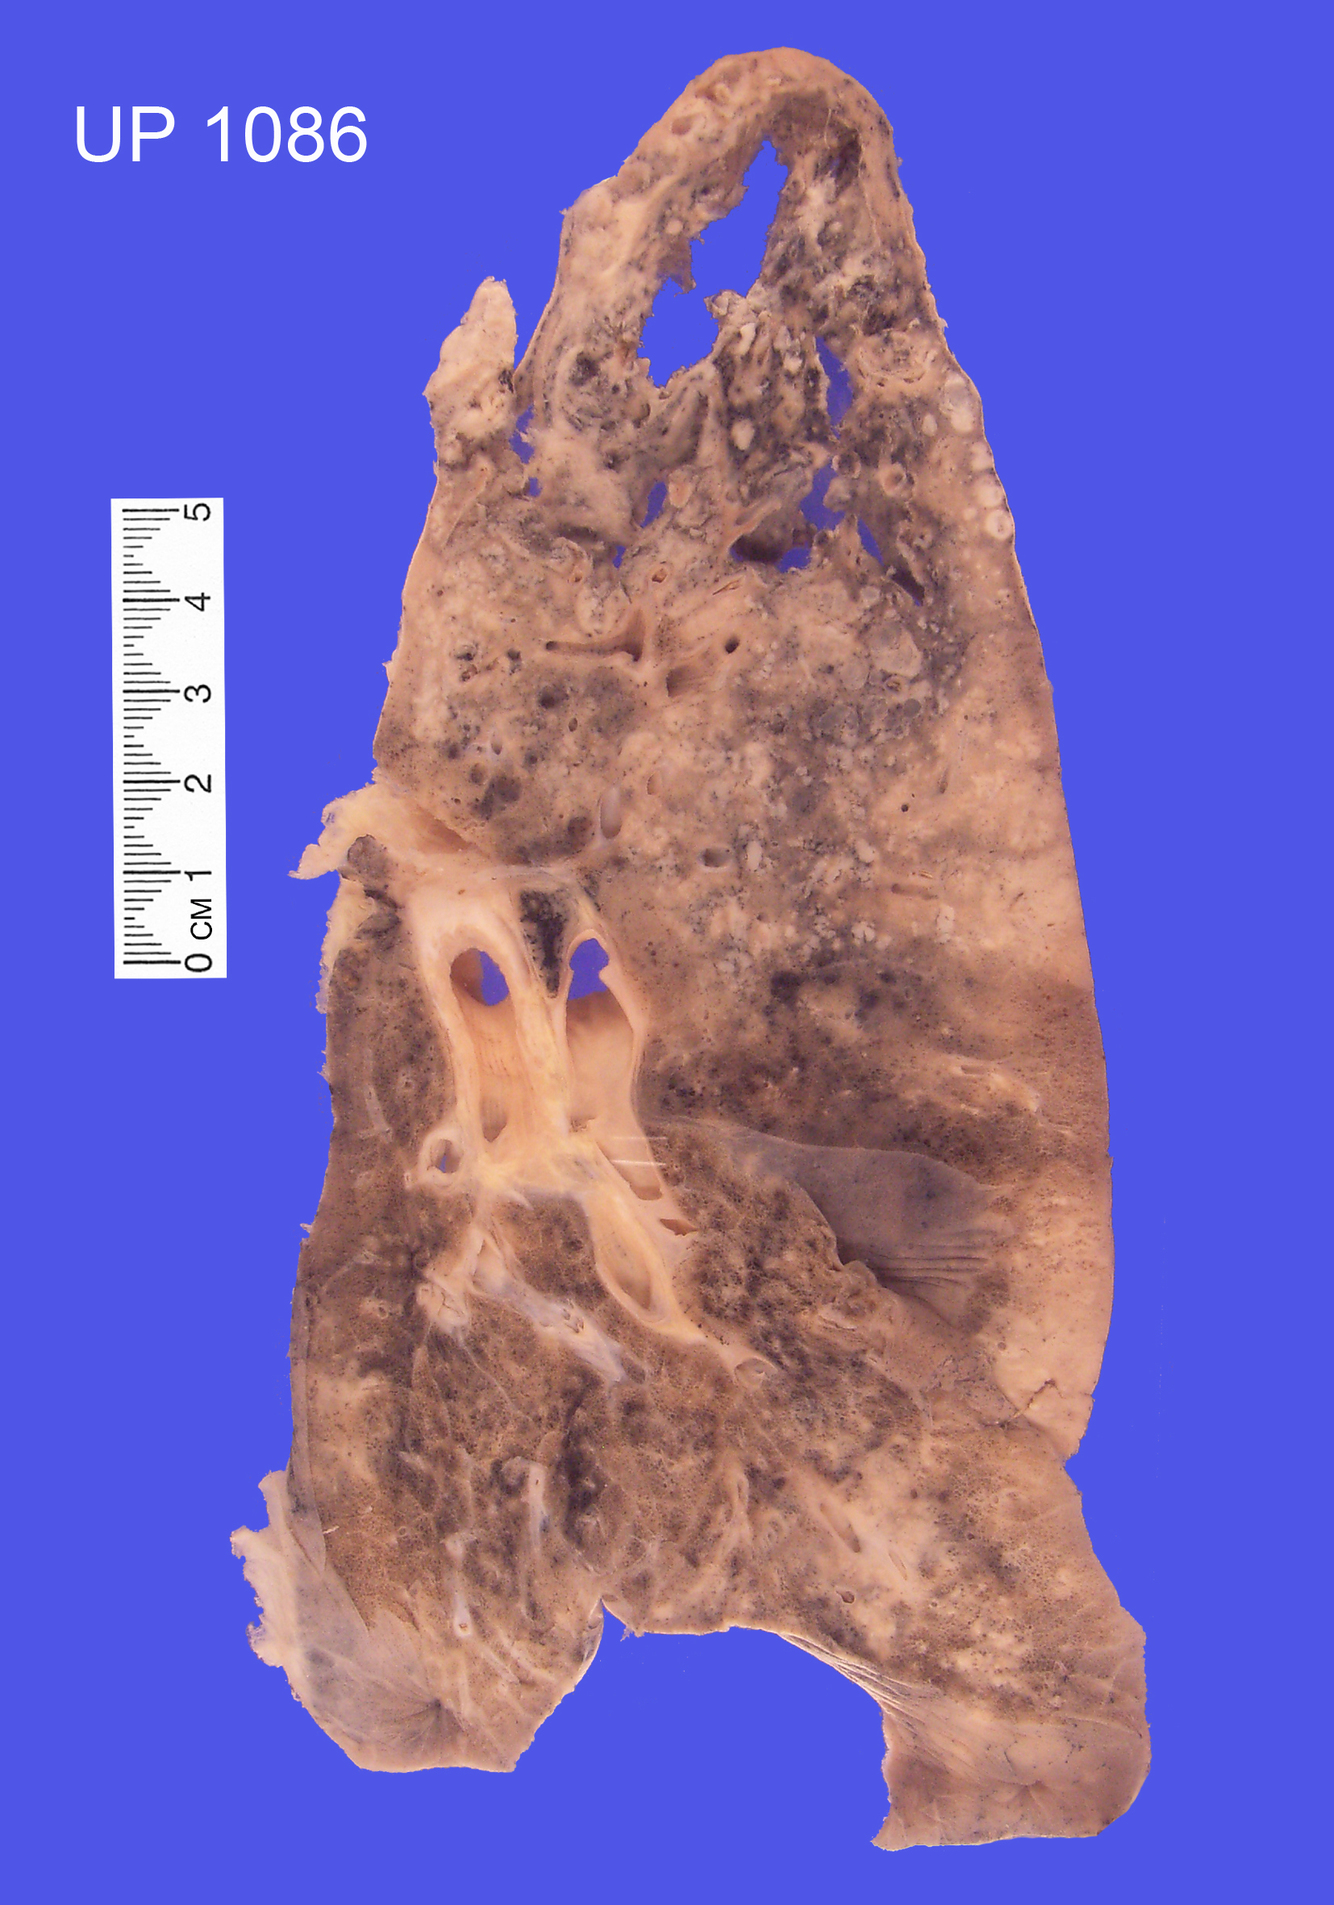

Specimen of left lung

Lung parenchyma shows honeycomb appearance, with large cyst-like spaces, particularly in upper lobe.

The lower lobe appears fibrotic

Usual Interstitial Pneumonia